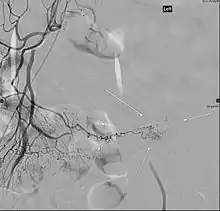

Patients with these misplaced gastric cells may experience peptic ulcers as a consequence. Therefore, other tests such as colonoscopy and screenings for bleeding disorders should be performed, and angiography can assist in determining the location and severity of bleeding. Colonoscopy might be helpful to rule out other sources of bleeding but it is not used as an identification tool.

Angiography might identify brisk bleeding in patients with Meckel's diverticulum.[17]